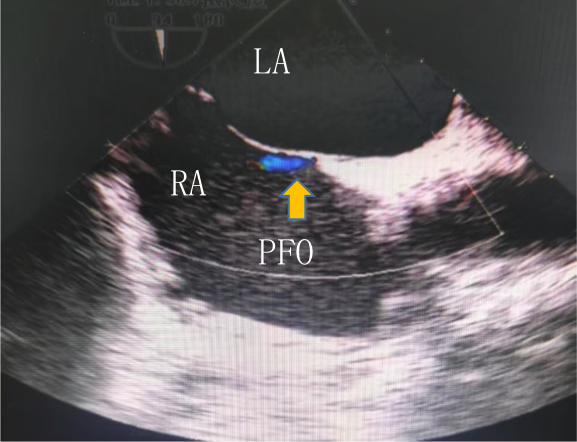

左图:经胸超声未发现卵圆孔未闭

右图:经食管超声发现宽约1.2mm的PFO